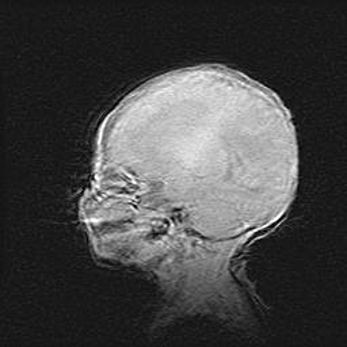

Наружная гидроцефалия с возможной атрофией височных областей.

Возраст: 28 дней

Вес: 3670 г

Пол: мужской

Окружность головы: 38 см

Срок гестации: 40 недель

Гидроцефалия головного мозга у новорожденных – это заболевание, которое характеризуется скоплением избыточного количества спинномозговой жидкости в желудочковой системе головного мозга в результате затруднения её перемещения от места выработки к месту поглощения в кровеносную систему или вследствие нарушения абсорбции. При открытой наружной форме гидроцефалии у новорожденных расширяются и переполняются субарахноидные пространства.

При нормотензивных  формах,  которые,  как  правило,  являются  следствием  перенесенных ишемических  повреждений  паренхимы  мозга,  возможно  сочетание микроцефалии  с нормотензивной гидроцефалией. В основе данных изменений лежит атрофия больших полушарий с преимущественной  локализацией  в  лобно-височных  областях.